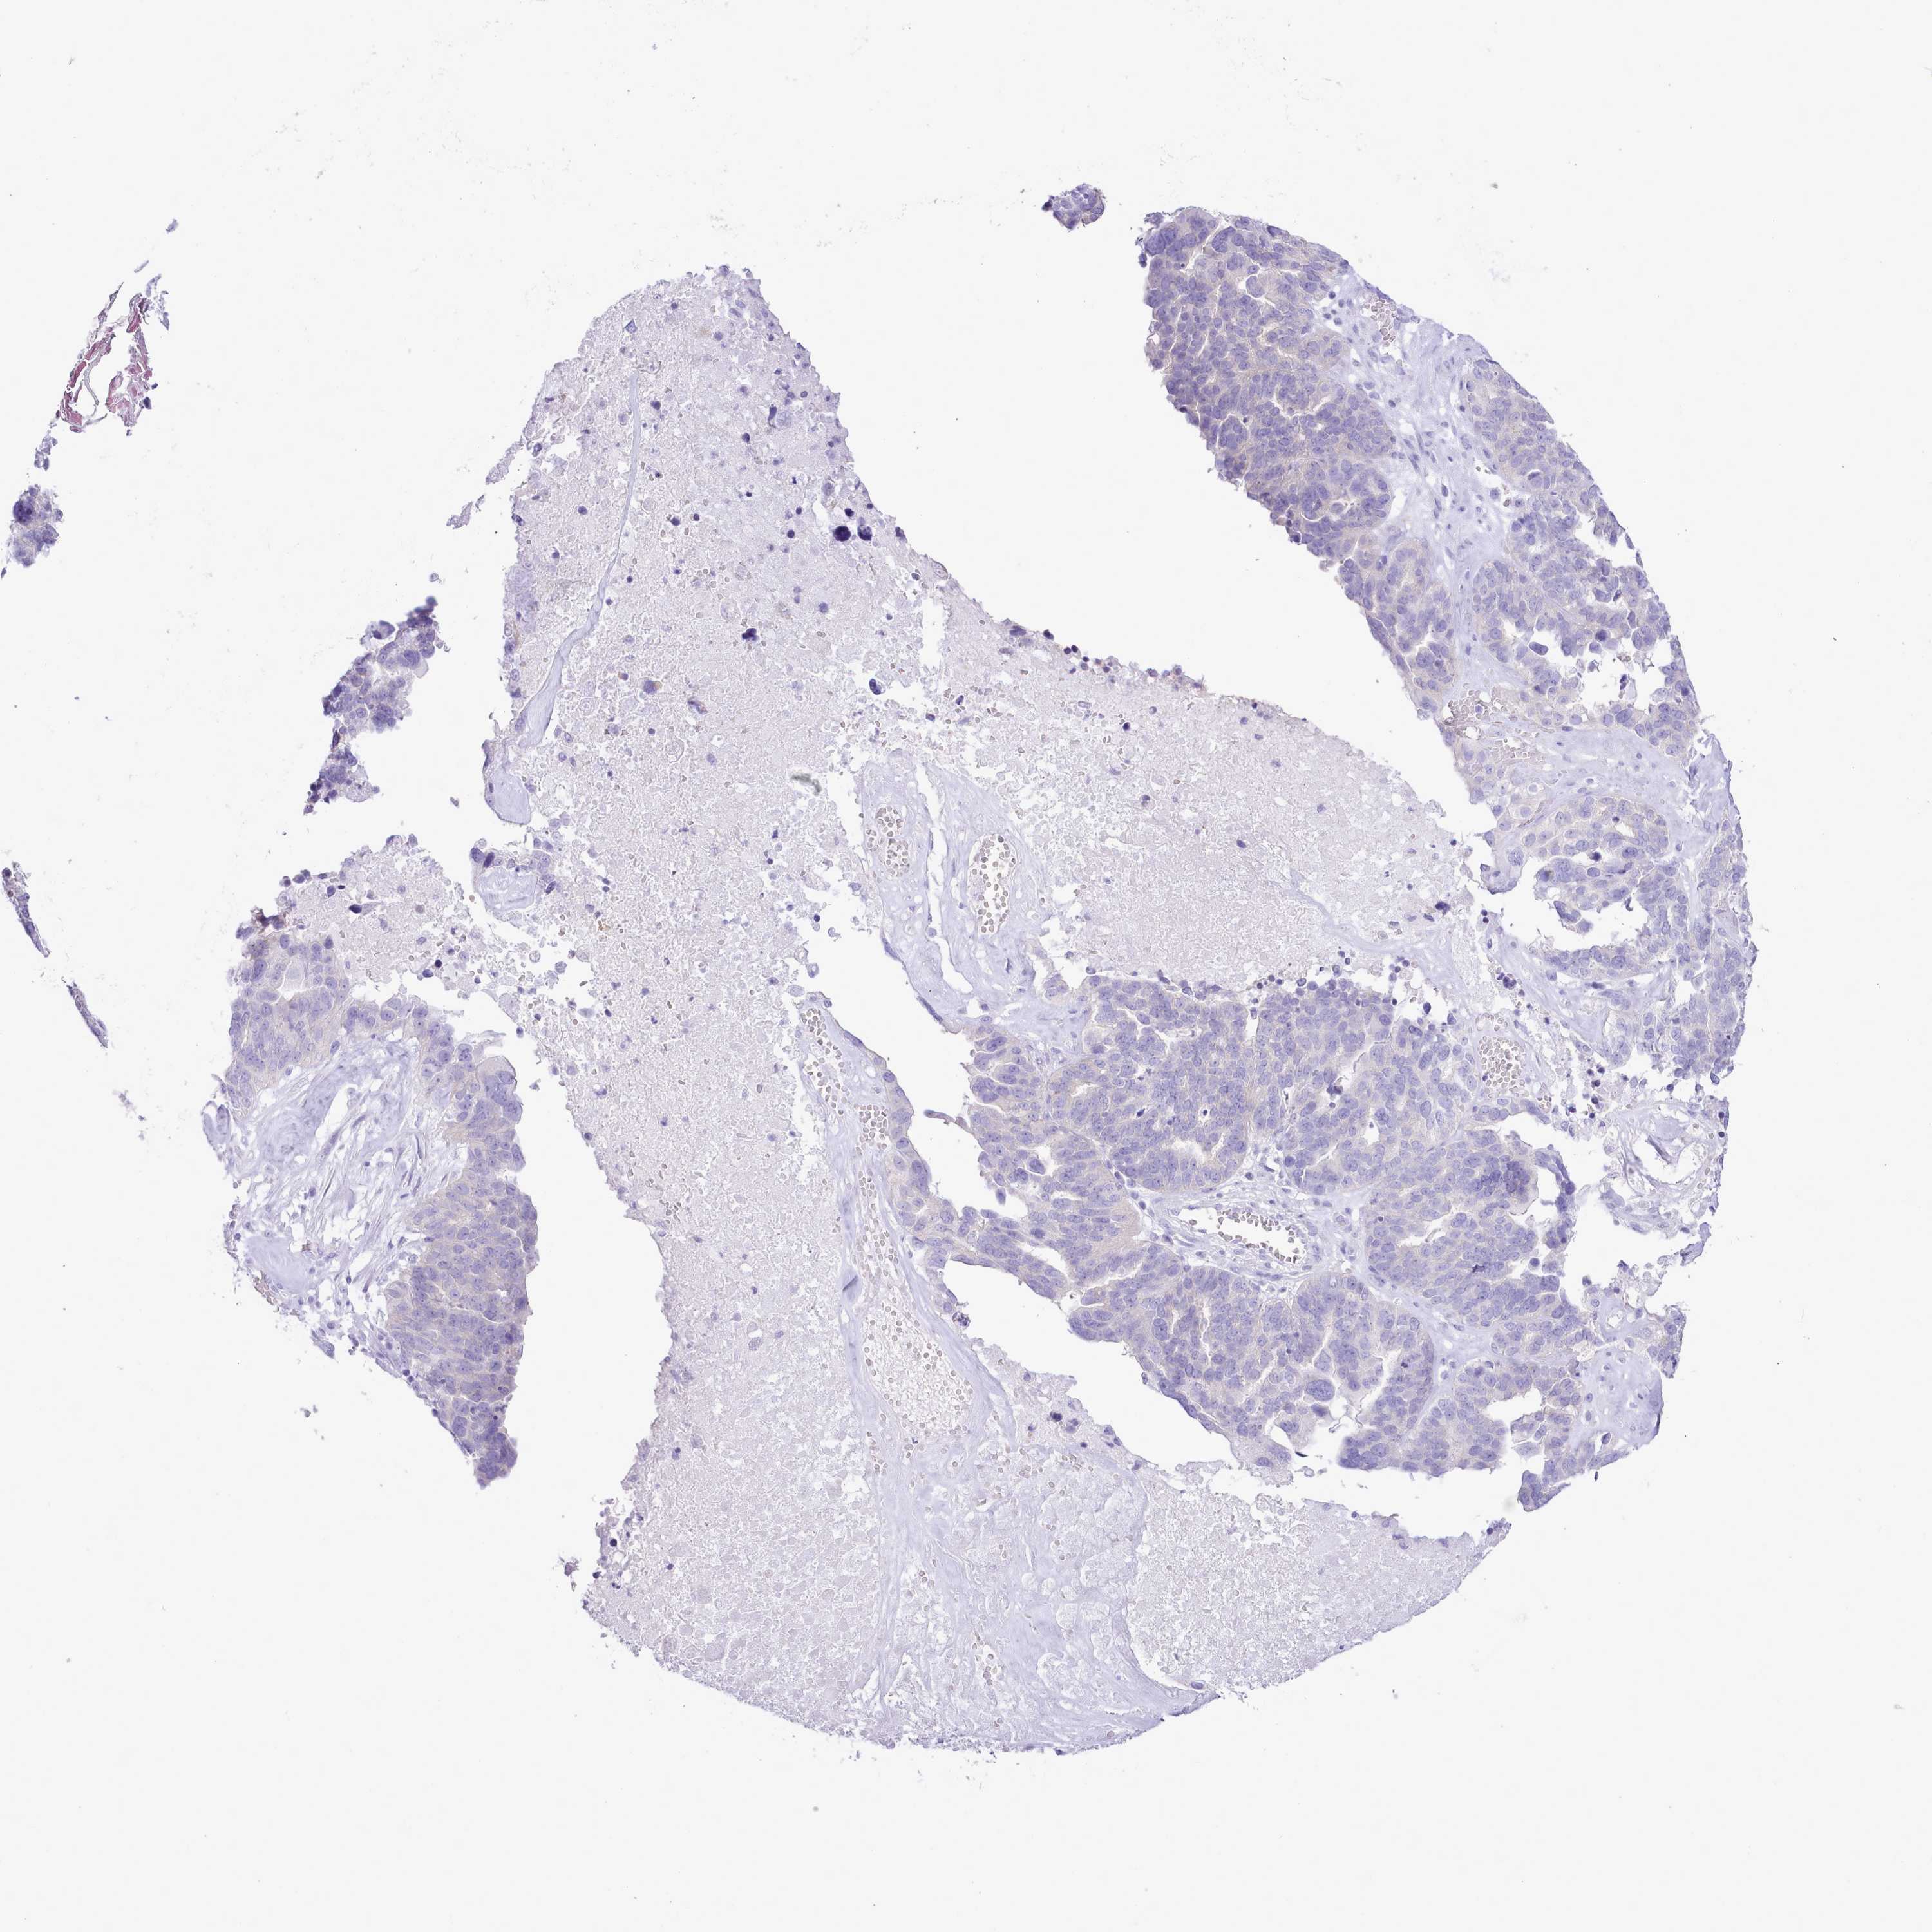

OVARIAN CANCER - Protein expressioni

A mouse-over function shows sample information and annotation data. Click on an image to view it in a full screen mode. Samples can be filtered based on level of antibody staining by selecting one or several of the following categories: high, medium, low and not detected. The assay and annotation is described here.

Note that samples used for immunohistochemistry by the Human Protein Atlas do not correspond to samples in the TCGA dataset.

Antibody stainingi

Antibody staining in the annotated cell types in the current human tissue is reported as not detected, low, medium, or high, based on conventional immunohistochemistry profiling in selected tissues. This score is based on the combination of the staining intensity and fraction of stained cells.

Each image is clickable and will lead to virtual microscopy that enables deeper exploration of all samples and also displays staining intensity scores, fraction scores and subcellular localization as well as patient and tissue information for each sample.

Antibody HPA049973

Staining

High

Medium

Low

Not detected

Intensity

Strong

Moderate

Weak

Negative

Quantity

>75%

75%-25%

<25%

None

Location

Nuclear

Cytoplasmic/membranous

Cytoplasmic/membranous,nuclear

Cystadenocarcinoma, serous, NOS

Carcinoma, NOS

Cystadenocarcinoma, mucinous, NOS

Carcinoma, endometroid